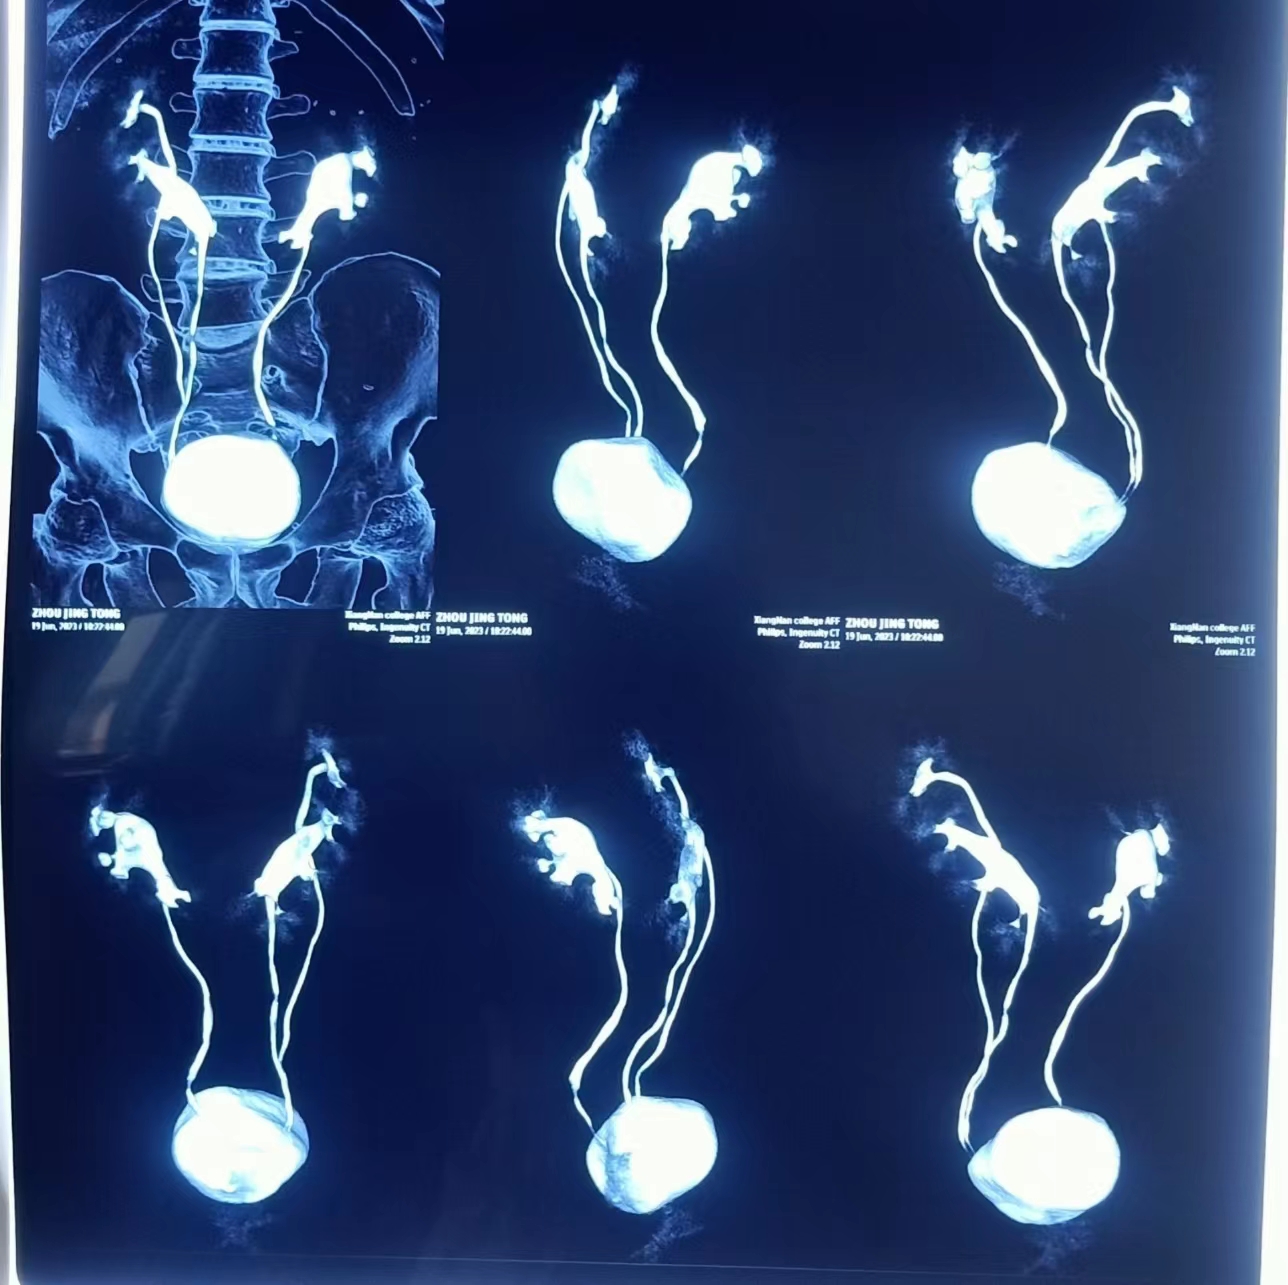

马蹄肾就是左右两边的肾脏,下部相互连接在一起,就像是一个英文字母'U’,医学上称之为'马蹄肾’,发病率约为0.25%,属于比较罕见的先天性肾脏发育异常。医学影像显示下,邹先生两侧肾脏的下端互相靠近,并彼此接触、融合,更为罕见的是,患者的马蹄肾居然还拥有双输尿管。唐建生介绍说,“马蹄形肾如果没有引起并发症,一般不会有明显症状,无症状者不必治疗,可维持正常生活,平时应避免过于激烈的对抗性运动。患者如果反复出现感染和结石,医生会根据患者融合肾的解剖结构制定相应的手术方案,松解输尿管,使尿流畅通。如肾功能受损严重或伴有癌变迹象,医生则会考虑将其切除,以免造成更大的危害。”

面对邹先生异于常人的马蹄肾,唐建生立即组织泌尿外科团队进行病例分析讨论,完善相关检查,结合CT和3D影像学检查,清楚的显示双肾盂输尿管畸形,其中左上位肾的输尿管全程明显扩张,左上位输尿管异位开口于前列腺,其排便改变与异位输尿管开口及扩张的输尿管刺激有关。经过详细周密的手术方案设计,医务人员决定通过微创手术为邹先生解决病痛。